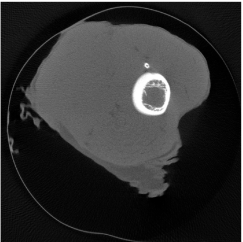

4.2 Numerical experiments: real data

We perform a CT scan of a chicken leg placed in a disposable cup (Figure 10(a)). We first scan the chicken leg without metals (Figure 10(b)) to create a reference image using FBP algorithm. Then, we place two steel thread nails on each side of the chicken leg and scan the subject again using the same scanning protocol (Figure 10(c)). The projection data is acquired from a MicroCT scanner equipped at the Division of Nuclear Technology and Applications, Institute of High Energy Physics, Chinese Academy of Sciences. The X-ray source is with 90 kV and 70 mA energy and the flat plane detector contains pixels. The scanning trajectory is a full circle with equally spaced views at per view. The physical size of each detector unit is . The distance from the X-ray source to the detector is . In order to conduct a 2D experiment, we choose the 512th row of the detector array.

Figure 11 shows the images reconstructed using FBP, the analysis model (2.12), the inpainting model (2.13) and the segmented image from the image obtained by (2.14). The reference image without metal implants are shown in Figure 11(a). All the images in this subsection are displayed within the grayscale interval . The segmented image shown in Figure 11(e) is used to estimate the weights needed in NMAR and the re-weighted JSR model.